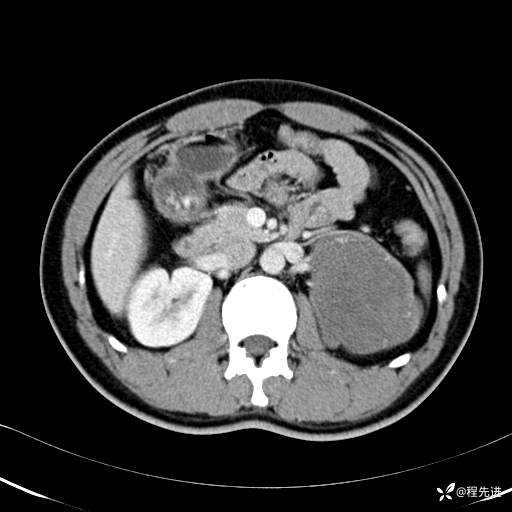

CT平扫:(CT值:平扫,27HU,动脉期,27HU,门静脉期,31HU,平衡期,32HU)

CT增强:

门静脉期: